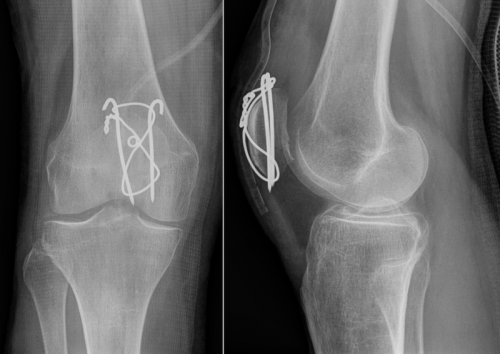

Discuss the management of patella fractures, include management of fractures which are:

Non-displaced or minimally displaced

Significatn displacement or disruption to extensor mechanism